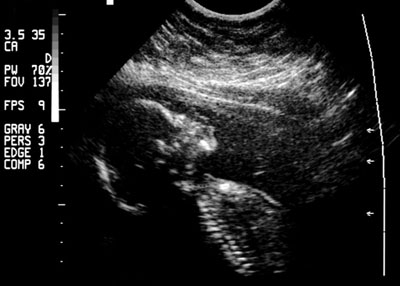

Женские органы размножения располагаются в нижней части живота, на уровне тазовых костей. В самом центре находится матка или, как ее еще называют, утроба, размеры которой в небеременном состоянии равны примерно пять на четыре сантиметра. Матка - небольшой мышечный орган, масса которого составляет примерно пятьдесят граммов, имеет грушевидную форму и направлена узкой частью вниз, где она соединяется с началом влагалища. Нижний конец матки заканчивается внутренним отверстием канала шейки, окруженным мышечной тканью, цервикальным каналом. Из верхней части матки исходят две трубы, направленные в стороны. Каждая труба имеет длину около семи - десяти сантиметров и на дальнем от матки конце завершается полостью в виде колокола. В основании каждого колокола находится небольшой овальный орган - яичник. Каждый из двух яичников содержит яйцеформирующую ткань. Каждый месяц яйцеклетка созревает и примерно через десять дней после менструации перемещается по трубе от яичника в матку. В это же время в матке создается специальная выстилка - удобное "гнездо" для оплодотворенной яйцеклетки. Если яйцеклетка не оплодотворяется, то она проходит через матку и выбрасывается наружу. Примерно через две недели выстилка матки тоже выбрасывается, и готовится новая для следующей яйцеклетки. Выброс неиспользованного материала называется менструацией. Мальчик рождается с яичками, которые незадолго до рождения с уровня поясничных позвонков опускаются в мошонку. В этом органе образуются сперматозоиды. Подсчитано, что каждое яичко содержит многочисленные семенные канальца, выстланные спермообразующей тканью, общей длиной около мили, причем здоровый мужчина за одну эякуляцию может выделить более двухсот миллионов сперматозоидов. В кульминационный момент совокупления мужская сперма выбрасывается из мочеиспускательного канала во влагалище женщины. Зрелый сперматозоид имеет длинный тонкий хвост, который позволяет ему продвигаться к отверстию в шейке матки. Скорость передвижения составляет примерно двадцать пять миллиметров в десять минут. Значительное количество сперматозоидов успешно проходят через матку в трубы и принимают участие в соревновании, главный приз которого - оплодотворение яйцеклетки. Как только оплодотворение происходит, яйцеклетка сразу же видоизменяется и делается недоступной для прочих сперматозоидов. Оплодотворенная яйцеклетка перемещается по трубе в матку, располагается на ее стенке и начинает расти. Выстилка матки претерпевает изменения - образуется детское место, или плацента, через которую мать питает плод. Плацентарная площадка быстро расширяется, интенсивно развиваются кровеносные сосуды и нервные волокна - начинается развитие ребенка. Вскоре после оплодотворения из яйцеклетки образуются различные по форме клетки, которые впоследствии развиваются в органы и части тела ребенка. На этом раннем этапе развития уже заложен пол будущего ребенка. Во время внутриутробной жизни плод защищен пузырем воды, в котором он и обитает. Воды защищают плод от повреждений (когда мать, например, падает или ударяется о что-либо), сохраняет постоянную температуру и предоставляет достаточное пространство для свободных перемещений, вплоть до последних дней беременности. Плод растет очень быстро, питается через пуповину, которая прикрепляется к плаценте. Этот удивительный орган - плацента - располагается на внутренней стороне матки и служит фильтром для крови матери. Плацента не только выделяет из крови то, что требуется ребенку, но и обладает свойством задерживать вещества, способные оказать вредное воздействие. К моменту рождения ребенка длина пуповины может составлять от тридцати сантиметров до одного метра.